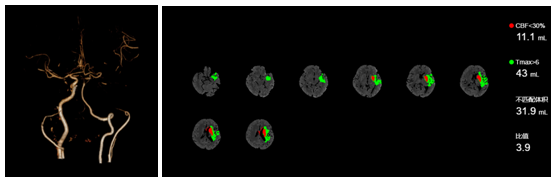

我院副院长刘芳自2013年起牵头建设卒中中心(神经内科、急诊科、血管科、神经外科、放射影像科、检验科),不断优化绿色通道救治流程及平台建设,提升再灌注治疗质量,结合早期神经康复治疗,减少了脑卒中致残率,显著提高了患者的生活质量。2023年,我院完成静脉溶栓160例,血管内治疗(动脉溶栓及取栓)33例(北京市排名第14位)。我院多模态高级影像和人工智能软件系统可筛选出醒后卒中(入睡时正常,但醒后出现卒中症状)仍存在缺血半暗带的患者,使其有机会得到静脉溶栓或介入取栓治疗,改善预后,缩短住院时间。

多模态高级影像